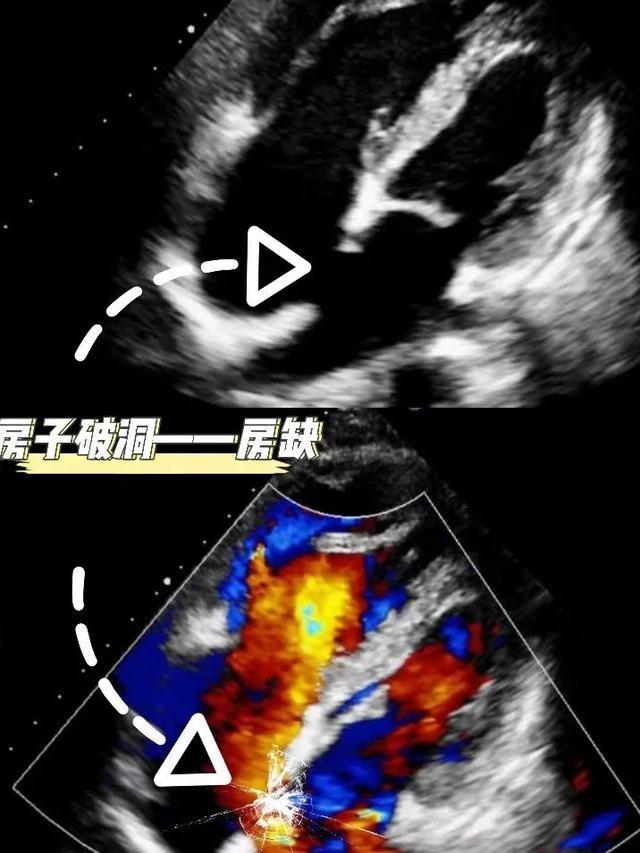

例如,心脏彩超主要检查房子(心房/室)是否增大,墙壁(房/室壁)是否增厚,墙壁是否出现孔洞(房/室缺),门窗(房室瓣、半月瓣)是否关闭良好,以及房子的稳固情况(心功能)等。

房缺